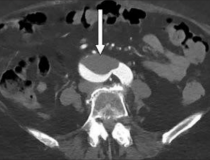

This photo gallery shows the variety of radiological presentations of COVID-19 (SARS-CoV-2) in medical imaging, including computed tomography (CT), radiograph X-rays, ultrasound, echocardiograms and magnetic resonance imaging (MRI). The radiology images show examples of typical COVID pneumonia in the lungs and the numerous complications the virus causes in the body in multiple organs, including the brain, kidneys, heart, abdomen and vascular system.

Ultrasound, especially hand-held ultrasound imaging devices, have become a primary imaging modality for novel coronavirus because of the ease to bag the device and sterilize it after use. CT and mobile X-ray systems are also used as front-line imaging systems for COVID-positive or suspected COVID patients.